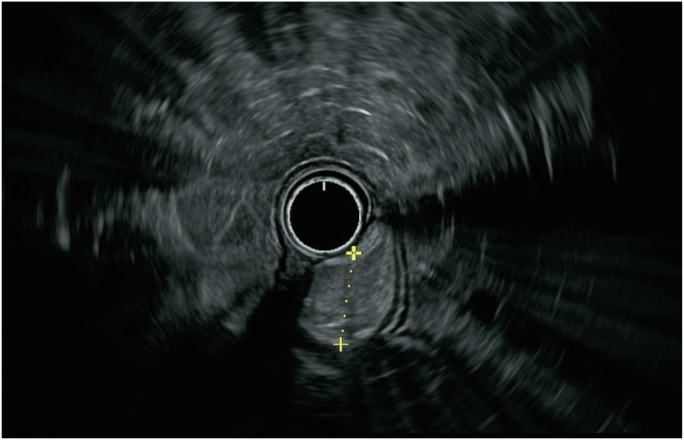

Figure 2.

Radial EUS demonstrated a hyperechoic mass with well-defined endosonographic borders arising from the submucosal layer, consistent with lipoma.